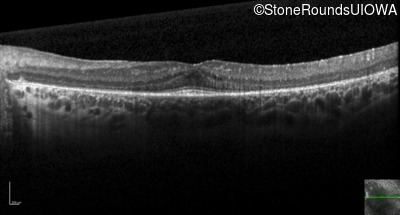

Optical Coherence Tomography - Right - 20/50

Exemplar / OCT Stack

OCT Stack